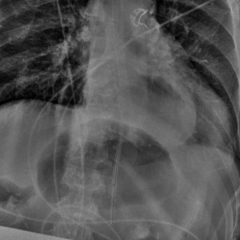

Bedside ultrasound with the transducer placed on the posterior right shoulder revealed an anterior dislocation of the right humerus. This is evident by displacement of the humeral head further away from the posteriorly placed ultrasound transducer, and appears deep to the glenoid cavity. In a posterior shoulder dislocation, the humeral head would appear closer to the transducer (and the near field of the ultrasound image) than the glenoid. Note that a hypoechoic, heterogeneous fluid collection is within the joint space, compatible with a hematoma. A right shoulder X-ray confirmed the anterior dislocation with no evidence of fracture. Under direct ultrasound guidance the glenohumeral joint space was injected with 10 mL of 2% lidocaine as an intraarticular anesthetic block. The right shoulder was reduced using continual traction. Post-reduction ultrasound demonstrated a successful shoulder reduction, depicted by the humeral head being relocated to its anatomical location, adjacent to the glenoid cavity, as noted on the ultrasound image. A hematoma remains present within the joint space. Successful shoulder reduction was further confirmed by X-ray. The patient’s arm was placed in a sling and she was discharged home with orthopedics follow-up.